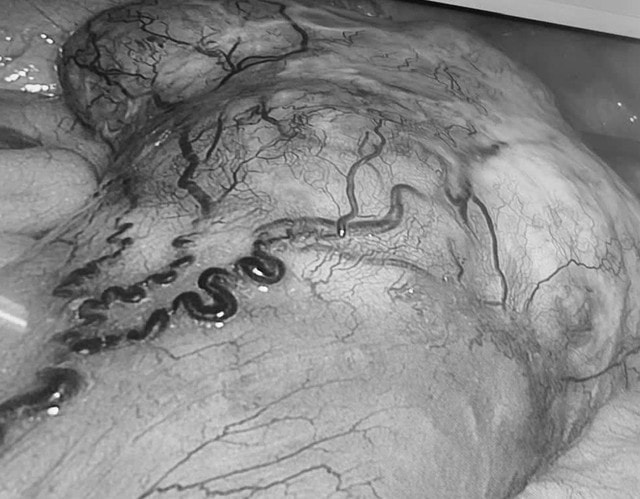

Tại Khoa Ngoại Tổng quát, Bệnh viện Đa khoa Vĩnh Long, bệnh nhân được các bác sĩ khai thác bệnh sử chi tiết, thăm khám lâm sàng kỹ lưỡng, đồng thời chỉ định thực hiện các cận lâm sàng chuyên sâu: Nội soi đại tràng ghi nhận tổn thương u sùi, gây hẹp lòng đại tràng, hình ảnh nghi ngờ ác tính. Chụp CT-scan ổ bụng phát hiện thêm một khối u đặc vùng hạ vị kích thước khoảng 10 x 10 cm, xuất phát từ ruột non, hình ảnh gợi ý u mô đệm đường tiêu hóa (GIST).

Sau 3 giờ can thiệp, hai khối u đã được cắt bỏ hoàn toàn mà không cần chuyển sang phẫu thuật mở. Ca mổ đảm bảo các nguyên tắc ung thư học, trong đó khối u đại tràng được cắt triệt căn, khối u ruột non nghi GIST được lấy trọn, không làm vỡ bao u. Lượng máu mất trong quá trình phẫu thuật ước tính khoảng 100 ml.